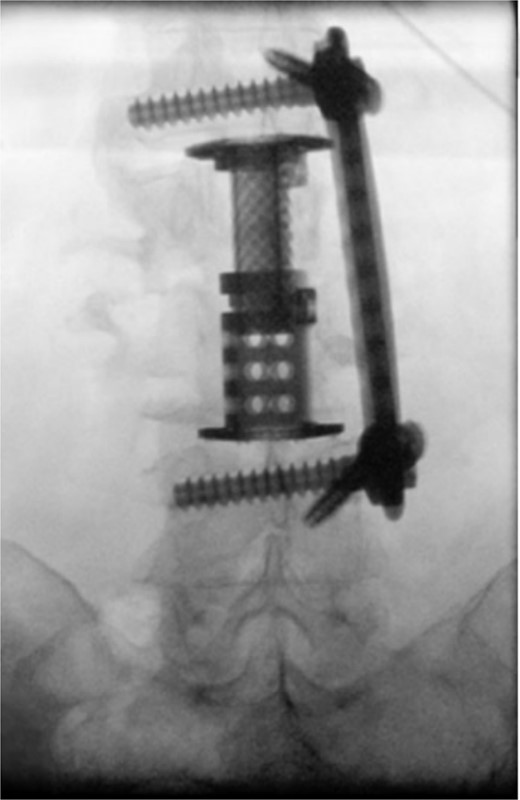

The patient was placed in the operating room for anterior lumbar interbody fusion via thoracoabdominal (TA) incision for retroperitoneal exposure. The patient was placed in the right-lateral decubitus position. The 10th rib interspace was identified, and a curvilinear incision was made from the midaxillary line and extended anteriorly and inferiorly toward the umbilicus. The retroperitoneal plane was entered, and the 11th rib was cut and morcellated for lumbar cage placement. The diaphragm was divided radially with electrocautery to further expose the abdominal cavity and retroperitoneal space. The lateral border of the psoas muscle was exposed and dissected into the anterior vertebrae L1–L4. The aorta and abdominal viscera were retracted toward the patient’s right side using an Omni retractor. Copious necrotic tissue and caseating granulomas were removed. The L2–L3 vertebrae were exposed, corpectomy was performed, and a titanium cage was placed with a plate spanning from L1 to L4 (Fig. 2A and B). To achieve added stability, a second surgery for posterior percutaneous screw placement without lumbar fusion was performed (Fig. 3). The patient recovered without complications and was subsequently discharged to a skilled nursing facility, and ultimately home. At the 1-month follow-up visit, the patient’s TA incision had completely healed, and there was no evidence of recurrent infection.

(A) Anterior intraoperative fluoroscopy demonstrating final titanium cage placement spanning from L1 to L4. (B) Lateral intraoperative fluoroscopy demonstrating final titanium cage placement spanning from L1 to L4.

Intraoperative fluoroscopy depicting two pedicle screws posteriorly placed in a percutaneous fashion with a 5.5 × 100 mm2 rod placed in the pedicle tulips.